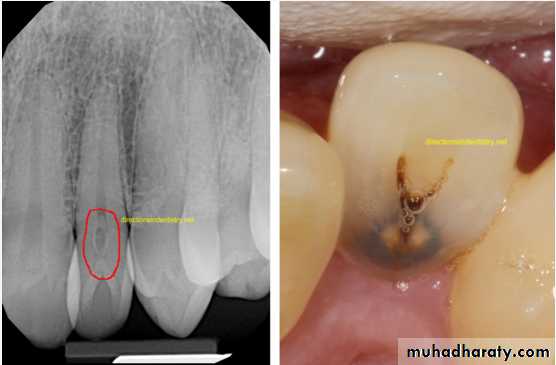

Dens in Dente (invaginated odontome) :

*It is an infolding of the outer surface of a tooth into the interior usually in the cingulum pit region of maxillary lateral incisors (tooth within a tooth).

*It is of 2 forms:coronal& radicular.

*Clinicaly varies from slight enlargement of cingulum

to a deep infolding that extends to the apex.

*Most cases of dens in dente are discovered radiographically. It is more radiopaque than the surrounding tooth structure and can easily be identified.